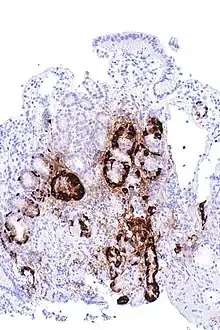

| Micrograph showing nodular enterochromaffin-like cell hyperplasia, as demonstrated with chromogranin A immunostaining, in the body of the stomach. Parietal cells are not readily apparent. These changes are in keeping with autoimmune metaplastic atrophic gastritis, a histologic correlate of vitamin B12 deficiency anemia. | |

PA may be considered as an end stage of autoimmune atrophic gastritis, a disease characterised by stomach atrophy and the presence of antibodies to parietal cells and intrinsic factor.[36][37] Autoimmune atrophic gastritis, is localised to the body of the stomach, where parietal cells are located.[34] Antibodies to intrinsic factor and parietal cells cause the destruction of the oxyntic gastric mucosa, in which the parietal cells are located, leading to the subsequent loss of intrinsic factor synthesis. Without intrinsic factor, the ileum can no longer absorb the B12.[38] Atrophic gastritis is often a precursor to gastric cancer.[37]